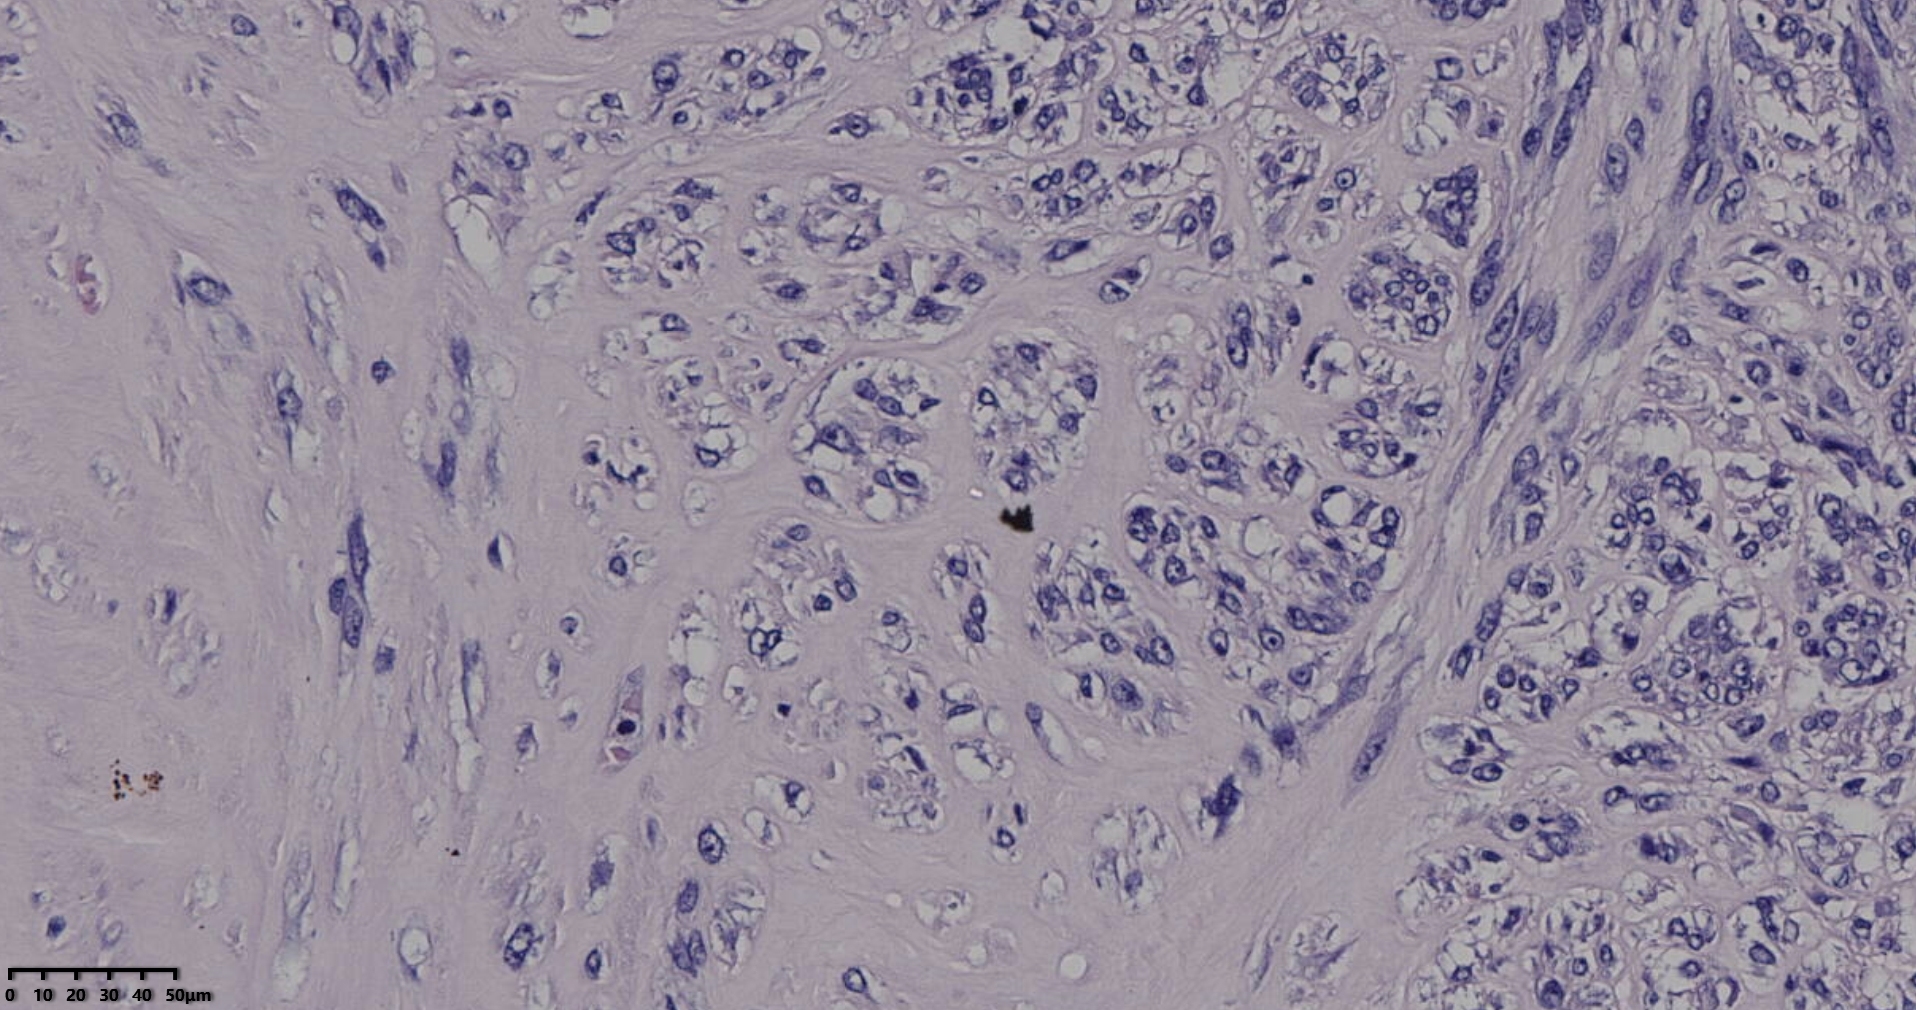

送检灰白肿物十余个,直径多在2-3厘米,切面均为灰白、实性,质地韧,其中一个大肿物,直径约7厘米,切片灰白灰红,质地韧当时取材时印象还是平滑肌瘤,伴变性,不考虑肉瘤,因为形态规整,质地韧,不脆,切面灰白,不是灰黄。

镜下所见小肿物无特殊,大肿物瘤细胞密集,中心区有变性、坏死,瘤细胞核有异型性。大肿物补充取材,发现,部分区域切面灰黄,这个区域,瘤细胞更密集,异型性更显著。肿物边缘有薄层正常平滑肌组织被覆,靠近边缘瘤细胞最密集,局部瘤组织内小血管较丰富。

会诊:考虑平滑肌肉瘤。

北医三院会诊:子宫平滑肌瘤伴红色变性可能性大,建议加做免疫组化及NGS检测进一步明确诊断。